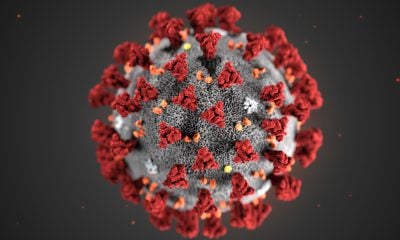

Vous n'avez sûrement pas pu passer à côté de l'épidémie de COVID-19 qui sévit en ce moment dans de nombreux pays. Vous pensiez être impuissant ? Détrompez-vous !